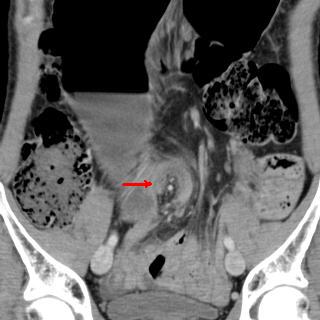

Occlusion du colon a cause

cancer du colon droit . Colon ascedante en amont de

lesion est tres dilate avec imcompetence de la

valvule Bauhin ( fleche jaunne ) .La masse du tumeur

est hyper-dense a bord irregulier (fleche rouge )

situe au colon pres de angle colique droite .

Le colon en aval est collapse . |

|

Meme cas en coupe axiale .

La masse du tumeur est hyper-dense a bord irregulier

( fleche rouge ) situe a la region sous hepatique

droit |